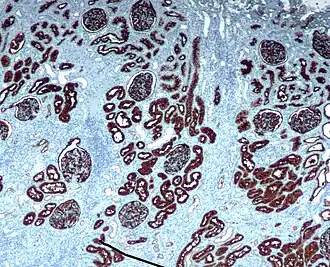

Inmunohistoquímica es una forma de inmunotinción que permite identificar selectivamente antígenos en células y tejidos, mediante anticuerpos que se unen específicamente a dichos antígenos. Albert Hewett Coons, Ernest Berliner, Norman Jones y Hugh J Creech desarrollaron la inmunofluorescencia por primera vez en 1941, lo que condujo posteriormente al desarrollo de la inmunohistoquímica.[2][3]

La inmunohistoquímica se usa ampliamente para diagnosticar células anormales, como las de tumores cáncerosos, y también en investigación básica para estudiar la distribución y localización de biomarcadores y proteínas expresadas diferencialmente en distintos tejidos.[4]

- **Cromogénicas**: enzimas (fosfatasa alcalina, peroxidasa) que producen un color al actuar sobre un sustrato como DAB.

Contracolorantes

Se aplican para dar contraste y facilitar la identificación de la morfología del tejido. Ejemplo: Hematoxilina.[6]

- ↑ Imagen por Mikael Häggström, MD. Terminología: Anjelica Hodgson, M.D., Carlos Parra-Herran, M.D. «p16». Pathology Outlines. Última actualización: 25 de enero de 2024